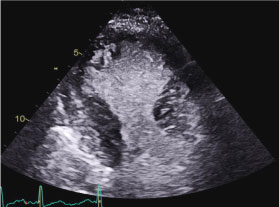

ECG revealed sinus tachycardia and non-specific ST changes (Figure 1). The echocardiogram revealed a left ventricle (LV) with a sigmoid septum and depressed LV systolic function (LVEF = 35%). Regional wall analysis revealed a hyperdynamic LV apical function and dyssynergy of the base (Figure 2 and Movie 1).

Figure 2: Apical 2 chamber end-systolic still frame revealing apical obliteration and basal akinesis. View Figure 2

Movie 1: Echocardiographic Apical 2 chamber view of the left ventricle with contrast revealing left ventricular hyperkinesia (red arrow) and left ventricular basal dyssynergy (yellow arrow). The echocardiographic features represent the subtype of stress-induced cardiomyopathy called reverse Takotsubo cardiomyopathy.